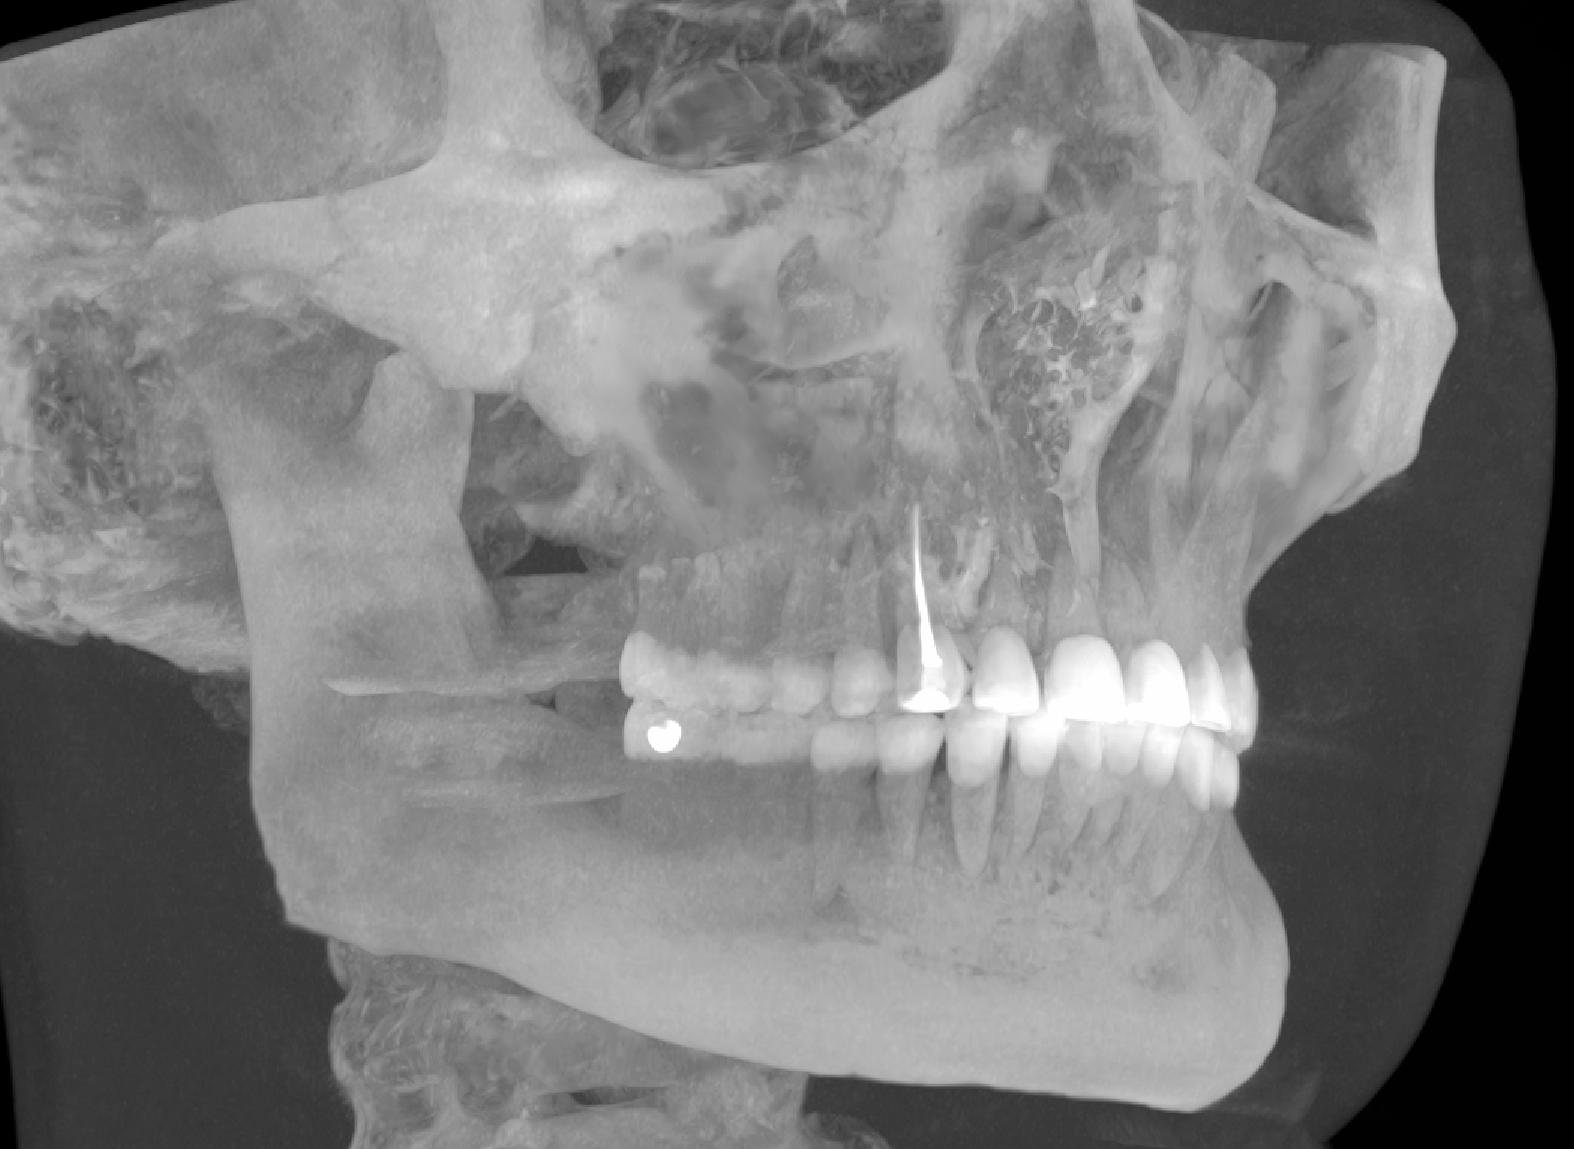

image.png

Я тут какую-то гигапломбу нашёл. чзх

Металл в черепе не отображается?

Рентген и программа металлы не определяет, не интересно